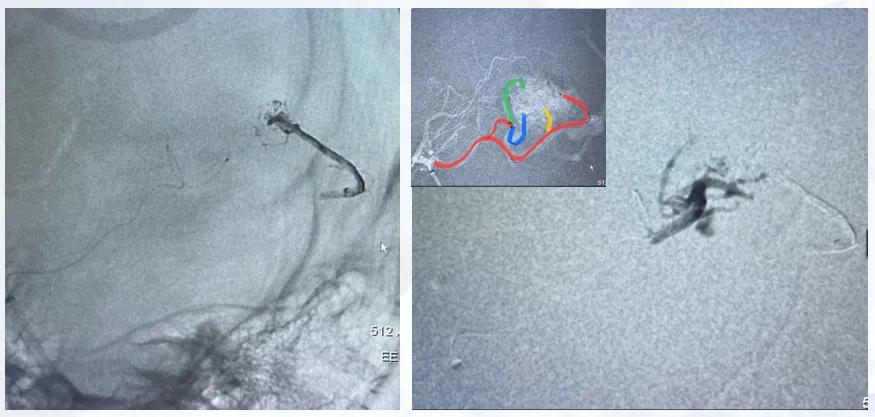

患者为少量出血,出血部位表浅,血管造影提示出血部位为小型动静脉畸形,供血动脉分支明确,引流静脉经海绵窦、翼状窦、乙状窦至上矢状窦。

图6 患者血管造影图

治疗策略:因病变表浅、体积小,未行术前栓塞,直接采取开颅手术切除畸形团,术中重点鉴别动脉与静脉,精准切除病变组织。

预后:术后患者恢复良好,皮层静脉恢复正常生理状态,未出现明显并发症,体现了表浅小体积病变直接手术切除的可行性。